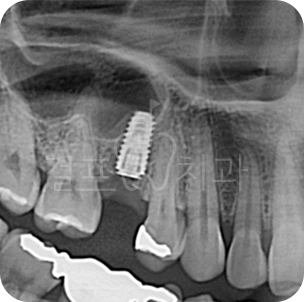

신속 정확! 발치 즉시 임플란트

환자가 원한다면 발치 즉시 임플란트로 잇몸뼈 소실을 줄일 수 있습니다. 임플란트 식립, 임시 보철물 제작까지 단 하루만에 가능합니다. ※ 케이스에 따라 식립기간은 달라질 수 있습니다.

• 치아 파절로 내원하신 분입니다. 잇몸뼈가 튼튼하신 분으로 발치즉시 임플란트가 가능하였습니다.

Before

After

• 치아 뽑은 자리 잇몸염증이 매우 심한 상태였습니다. 잇몸상태가 좋지 않아도

발치 즉시 임플란트를 시도할 수 있습니다. 다만, 2~3달 지난 후 수술한다면 더 안전하므로 이런 경우 즉시 식립을 추천드리지 않습니다. 발치 몇 달 후 상악동 거상술과 뼈이식 임플란트를 함께하여 수술을 완료하였습니다.